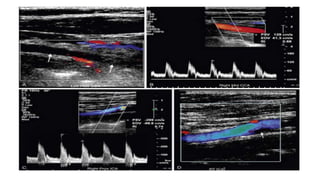

PSV- 195 CM/SEC PSV-96CM/SEC

PSV-305 CM/SEC PSV-85 CM/SEC

PSV- 195 CM/SECPSV-96CM/SEC

• #30 The angle of spectral Doppler insonation should be kept between 45 and 60 degrees to minimize error in the calculation of velocity from the Doppler frequency shift. When the Doppler angle (yellow circles) is 44 degrees (A), PSV is calculated at 131 cm/sec. However, with a Doppler angle of 60 degrees (B), PSV is 190 cm/sec; and when the Doppler angle is 70 degrees (C), PSV is calculated at 266 cm/sec. Thus, an incorrect Doppler angle or variations in Doppler angle from examination to examination can introduce significant error into the measurement of PSV.